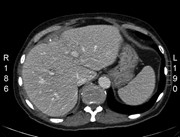

Concurrent hepatic hemangioma and solitary fibrous tumor: diagnosis and management

Michael Kueht and others

Journal of Surgical Case Reports, Volume 2015, Issue 7, July 2015, rjv089, https://doi.org/10.1093/jscr/rjv089